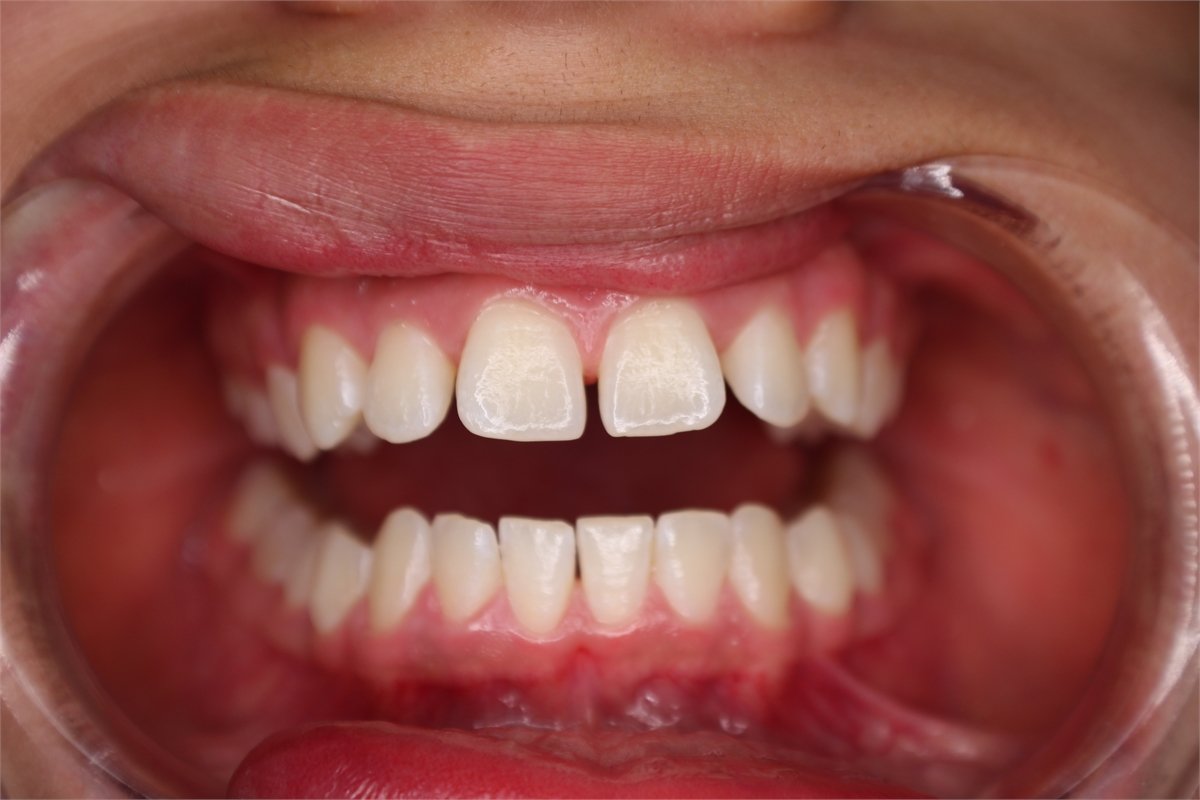

Many of us are not born with picture perfect teeth. For the straight teeth and alignment many people are searching for, braces is a common and effective treatment. Precision Dental Care uses the latest X-Ray technology to trace and model your teeth for your unique dental needs. From crooked teeth to alignment issues, braces can solve a variety of oral concerns.

Before and After Gallery